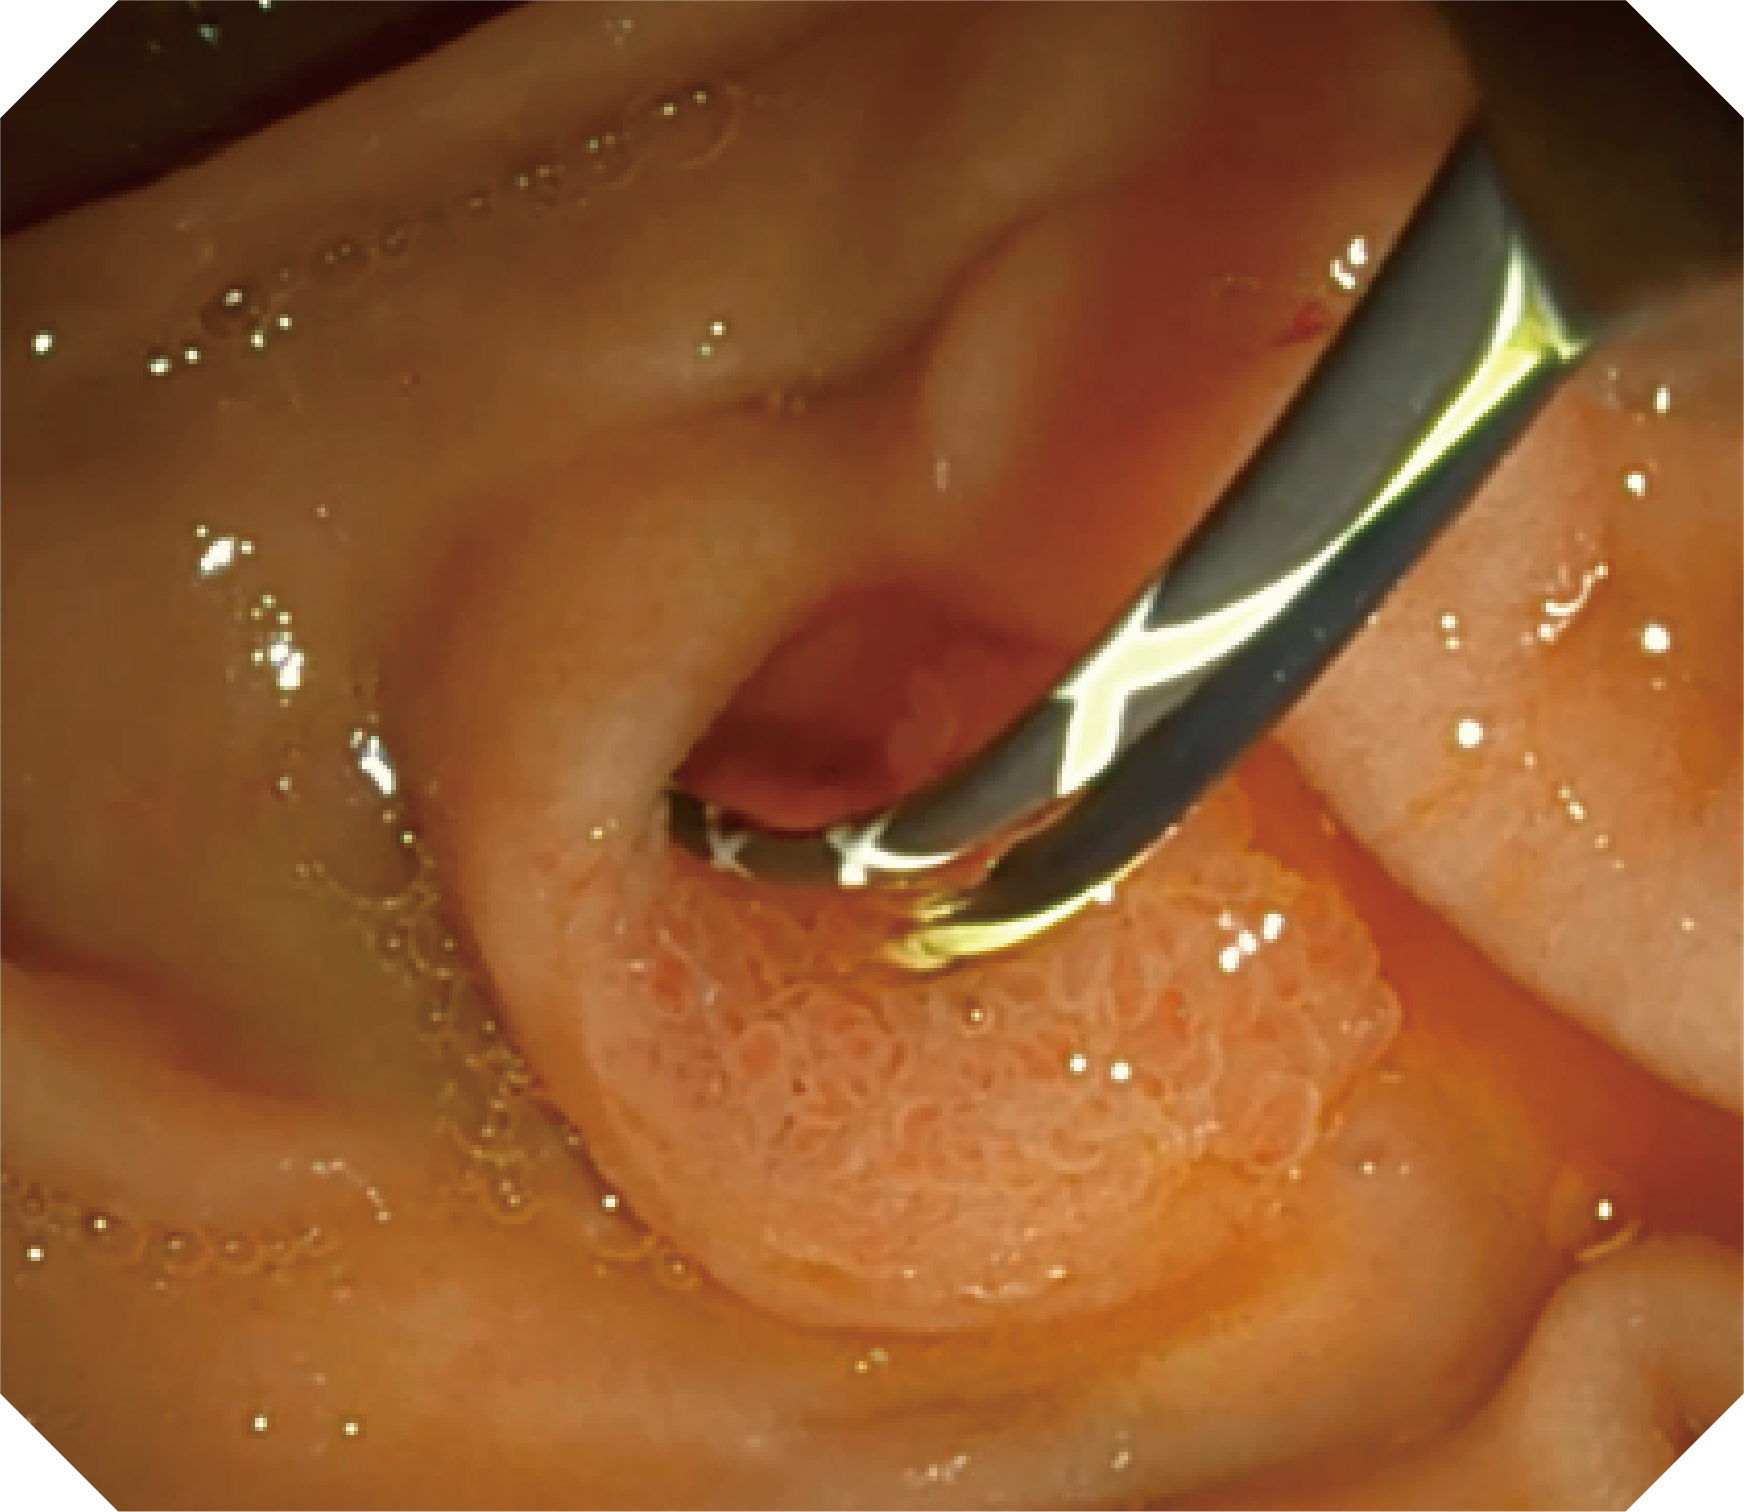

优异的手术器械抬举性

当切开刀伸出视野外时,导向面引导其回归视野